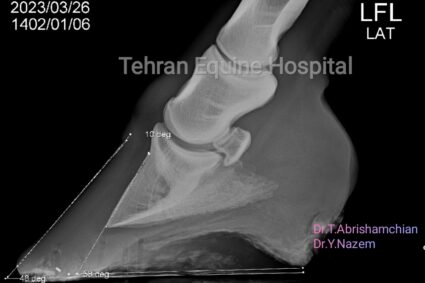

laminitis

by Dr Tooba Abrishamchian

November 15, 2023 0 2 yrs

Chronic laminitis

by Dr Yaser Nazem

November 10, 2023 0 2 yrs